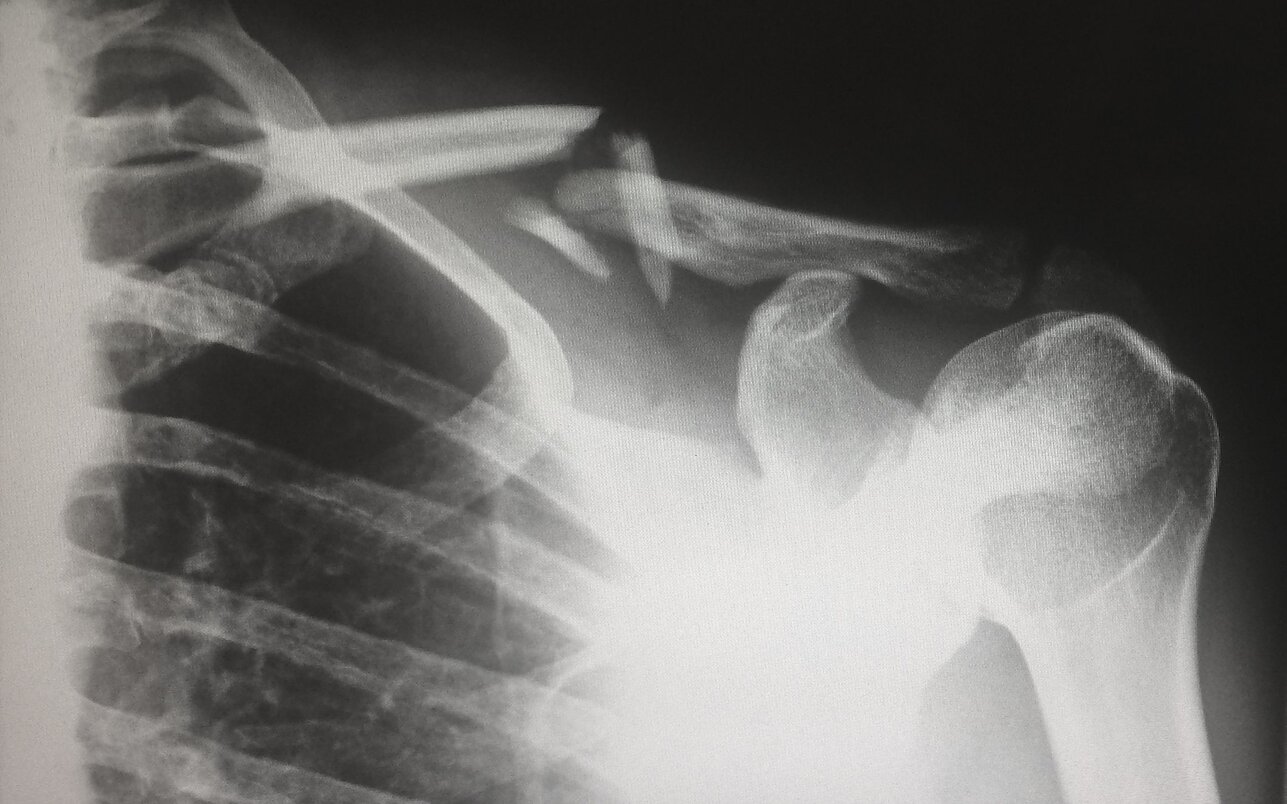

Atviras lūžis

Daivos Čepauskaitės radijo spektaklis „Atviras lūžis“. Režisierė Inga Tamulevičienė.